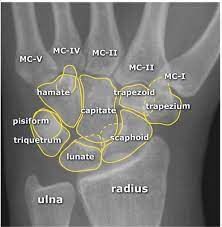

Carpal Bones Radiograph Labeled - Carpal Bones Mnemonic Anatomy Nursing And Medical Notes Basic Anatomy And Physiology Human Anatomy And Physiology Medical Knowledge : Carpi), are the eight bones of the wrist that form the articulation of the forearm with the hand.. The normal carpal bone angles were determined using the bone axes with the least observer variability (mean and range): Proximal row scaphoid lunate triquetrum pisiform. Swipe right for the answers! Start studying carpal bones labeling anatomy. The other four, superior or brachial, inferior or metacarpal , external or.

Carpal Bones Wikipedia from upload.wikimedia.org Drag the slider over the image to reveal or remove the highlighted bones of the radiograph labels: Only the proximal carpal bones are labeled and the distal ulna and radius. Pa radiograph of the wrist. Articulates with ulnar carpal bone. Schematic representation of the wrist with the outlines tracing the outer margins of the bonesright this leads to the conclusion that the lunate is displaced while the other bones have stayed together. They are usually divided into two rows: (a) distal phalanx 1st digit, (b) interphalangeal joint, (c) proximal phalanx 1st digit. Start studying carpal bones labeling anatomy.

Carpi), are the eight bones of the wrist that form the articulation of the forearm with the hand. The term carpus is derived from the latin carpus and the greek καρπός (karpós). Triangular appearance of lunate on frontal projection. Study the carpal bones as pieces of a jigsaw puzzleleft: Capitate and all other carpal bones lie posterior to lunate on lateral radiograph. The carpus is a composite joint composed of all the articulations to which the seven carpal bones contribute. Occurs when the lunate maintains normal position with respect to the distal radius while all other carpal bones are dislocated posteriorly. The carpal bones are the eight small bones that make up the wrist (or carpus) that connects the hand to the forearm. An easy and convenient way to make label is to generate some ideas first. The carpal bones are the eight bones of the wrist that form the articulation of the forearm with the hand. If an abnormal alignment of the carpal bones is depicted during imaging of the. Articulates with ulnar carpal bone. Dynamic instability is present if the carpal bones appear normal in standard radiographs taken at rest, but abnormal movement is identified in clinical examination, radiographic stress views, or cineradiography.

I Examination Of The Wrist Surface Anatomy Of The Carpal Bones Sciencedirect from ars.els-cdn.com They are usually divided into two rows: If an abnormal alignment of the carpal bones is depicted during imaging of the. Start studying carpal bones labeling anatomy. (a) distal phalanx 1st digit, (b) interphalangeal joint, (c) proximal phalanx 1st digit. The carpal bones, also known as the carpus (plural: Capitate and all other carpal bones lie posterior to lunate on lateral radiograph. The carpal bones are the eight bones of the wrist that form the articulation of the forearm with the hand. The distal row articulates with the bases of the metacarpal bones forming the pa hand radiograph above have the following structures labeled:

The carpal bones are a group of eight, irregularly shaped bones carpal bones labeled. Drag the slider over the image to reveal or remove the highlighted bones of the radiograph labels: